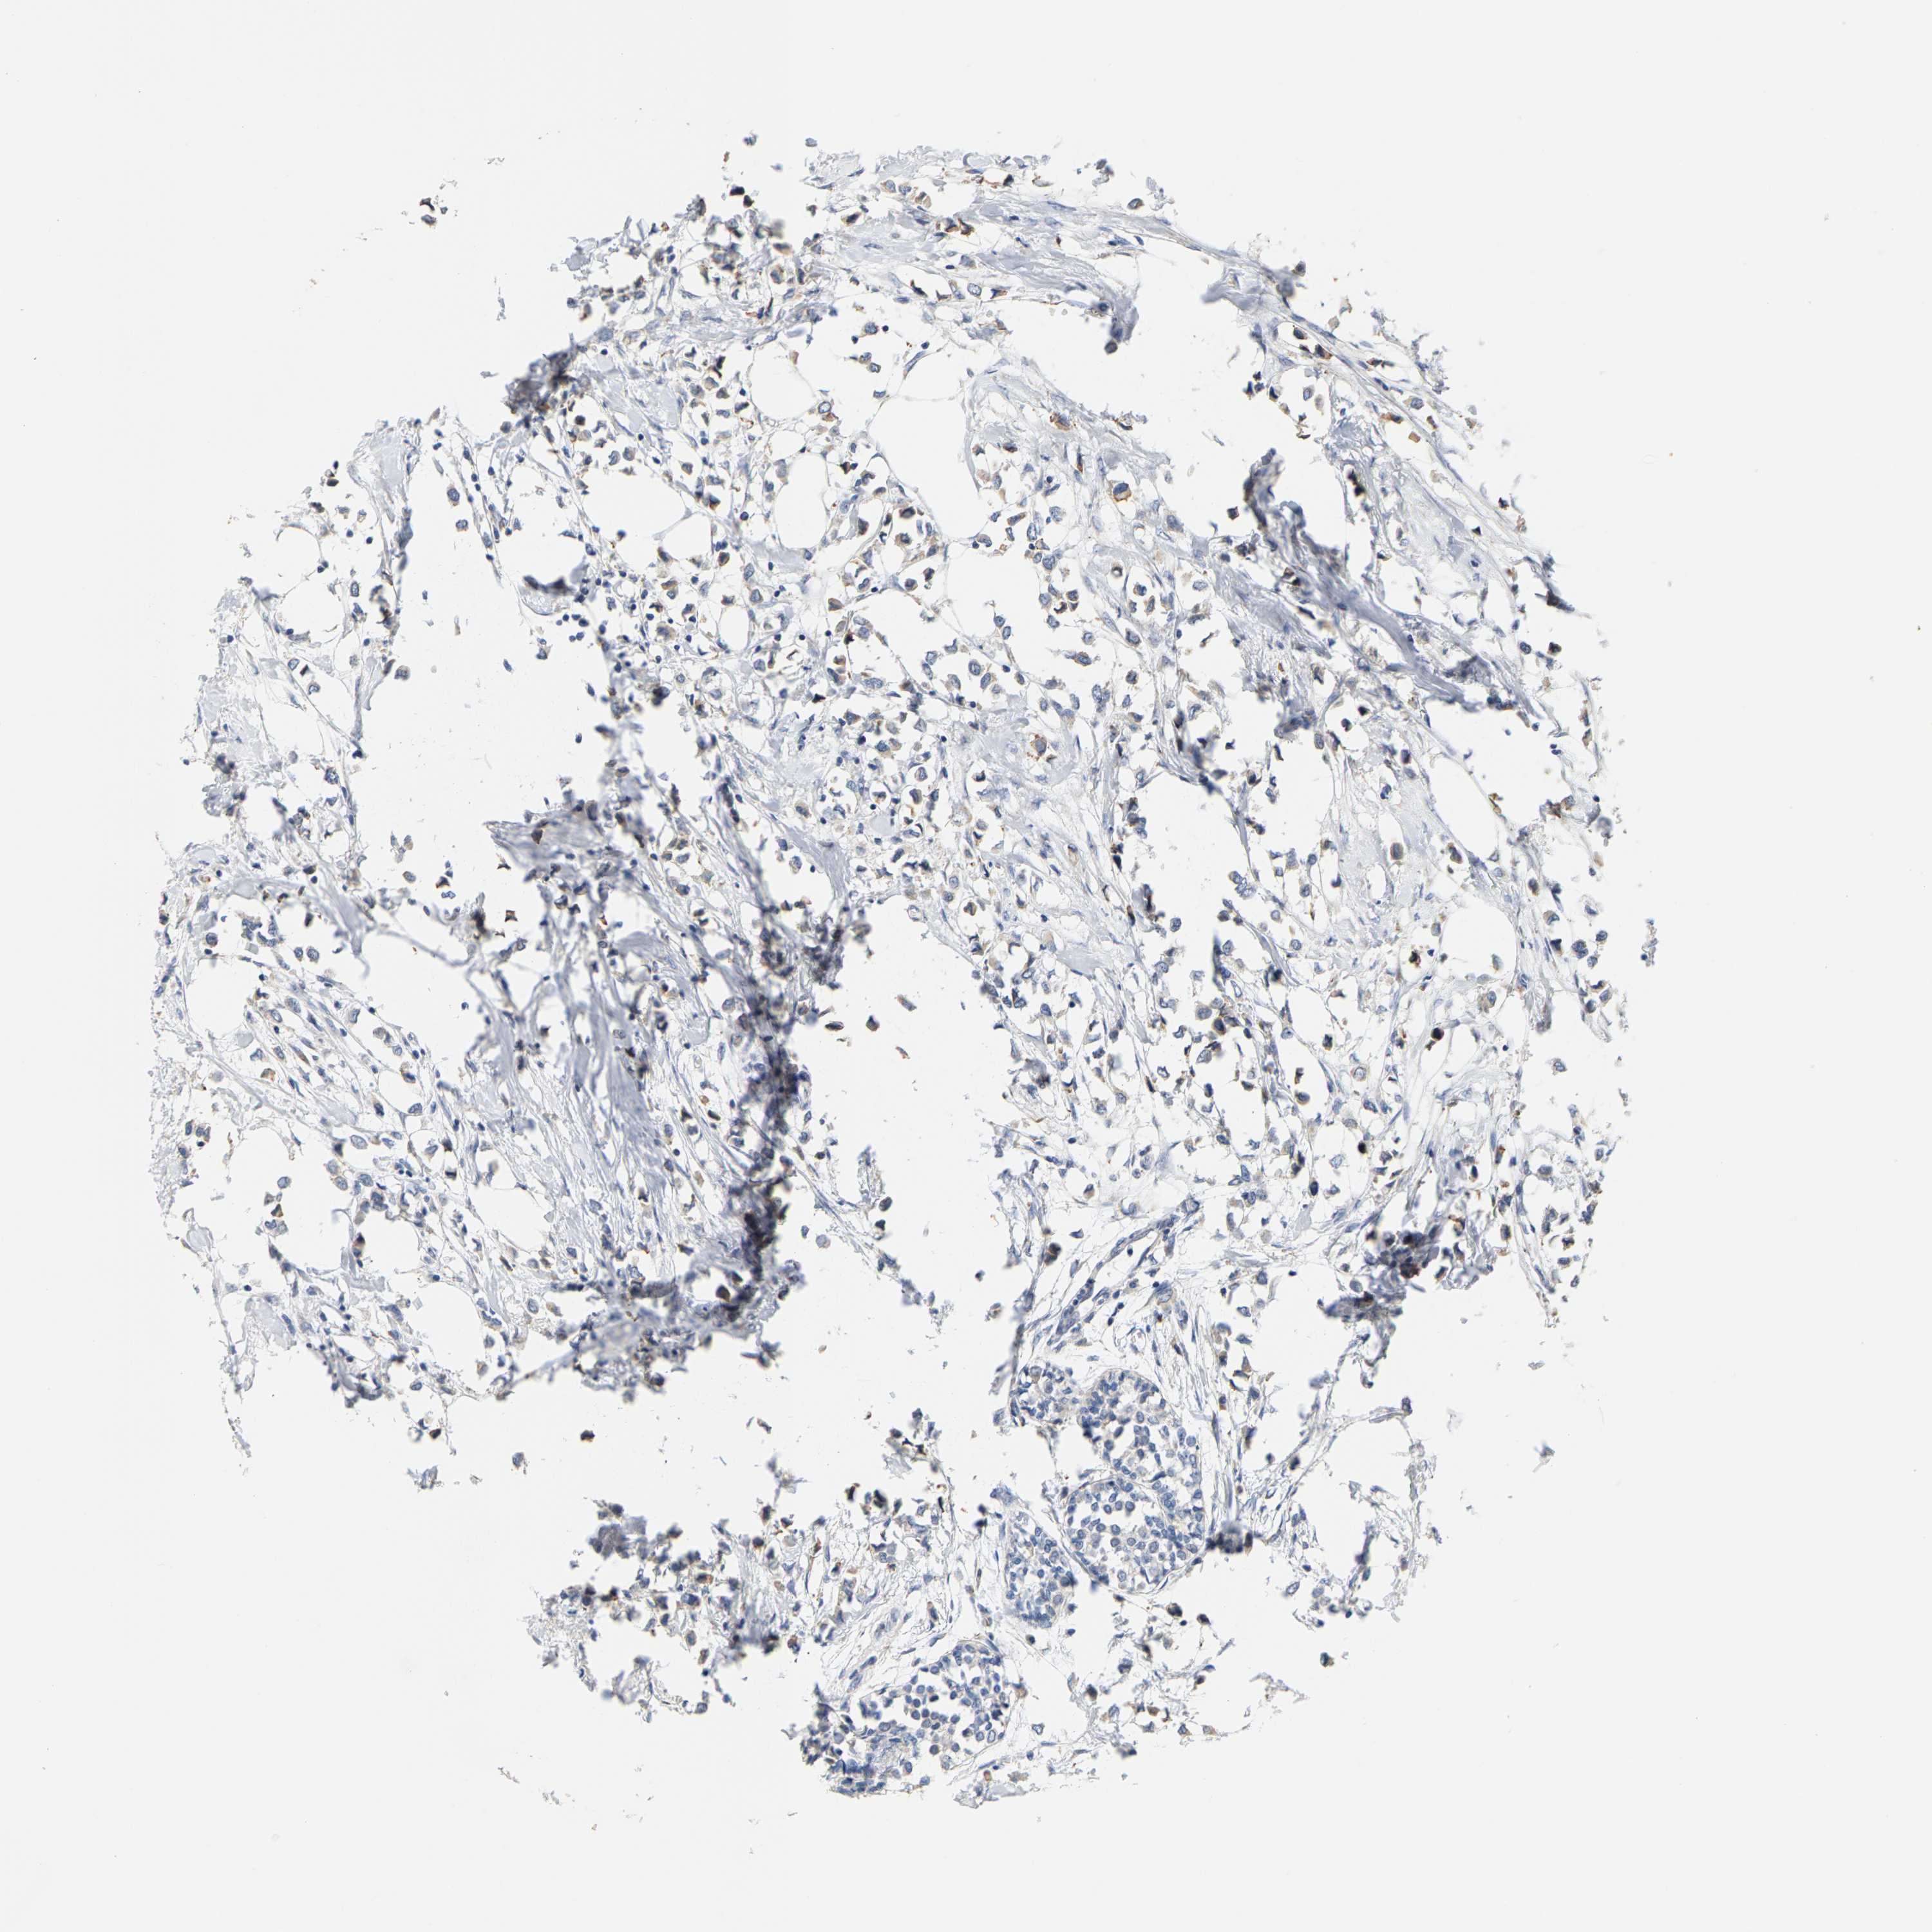

CANCER BREAST CANCER Show tissue menu

BRCA TCGA BRCA VALIDATION PROTEIN EXPRESSION